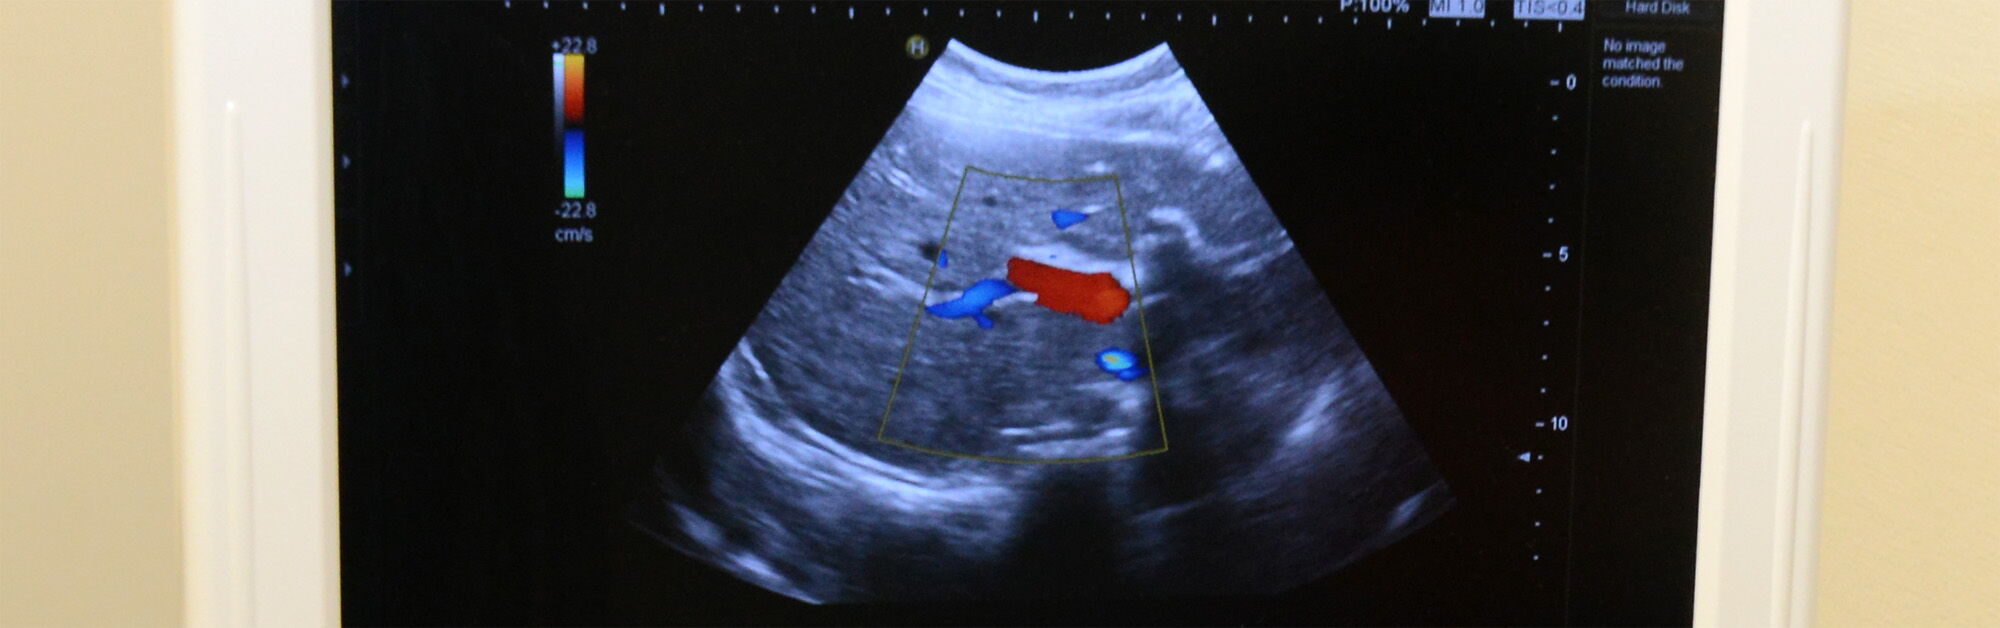

Bauch-Ultraschall (Abdomensonografie)

Der Bauchultraschall ist eine äußerst wertvolle Untersuchungsmethode, die dem erfahrenen Untersucher eine hervorragende Beurteilung der inneren Bauchorgane ermöglicht. Durch den Einsatz von hochfrequenten Schallwellen werden Nieren, Gallenblase, Gallenwege, Leber, Milz, Darm und Bauchspeicheldrüse detailliert untersucht. Insbesondere bei unklaren Bauchschmerzen ist der Bauchultraschall ein unverzichtbarer Baustein in der Diagnostik.